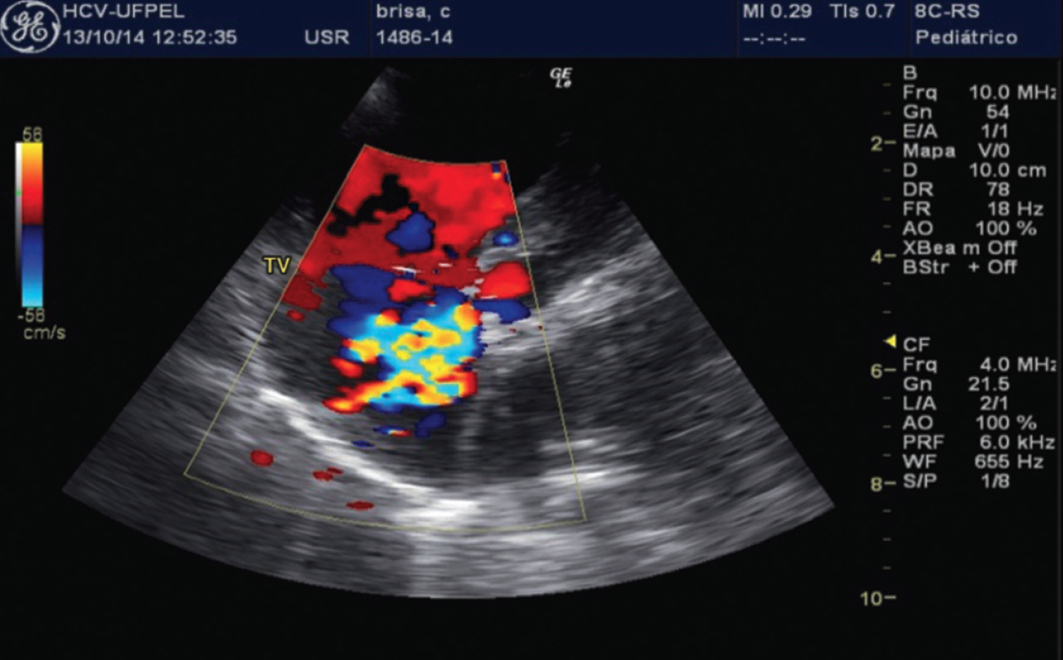

O diagnóstico de doenças cardíacas em cães envolve um exame físico completo pelo veterinário, ausculta cardíaca para identificar sopros e arritmias, e exames complementares. Radiografias torácicas ajudam a avaliar o tamanho e a forma do coração e a detectar fluidos nos pulmões. Eletrocardiograma (ECG) avalia a atividade elétrica do coração, e o ecocardiograma (ultrassom cardíaco) é a ferramenta mais precisa para visualizar a estrutura e a função cardíaca em tempo real. O manejo é individualizado e pode incluir medicações, dietas terapêuticas e modificações no estilo de vida, sempre sob supervisão veterinária. Lembre-se, a consulta com um veterinário é indispensável para qualquer diagnóstico ou plano de tratamento.